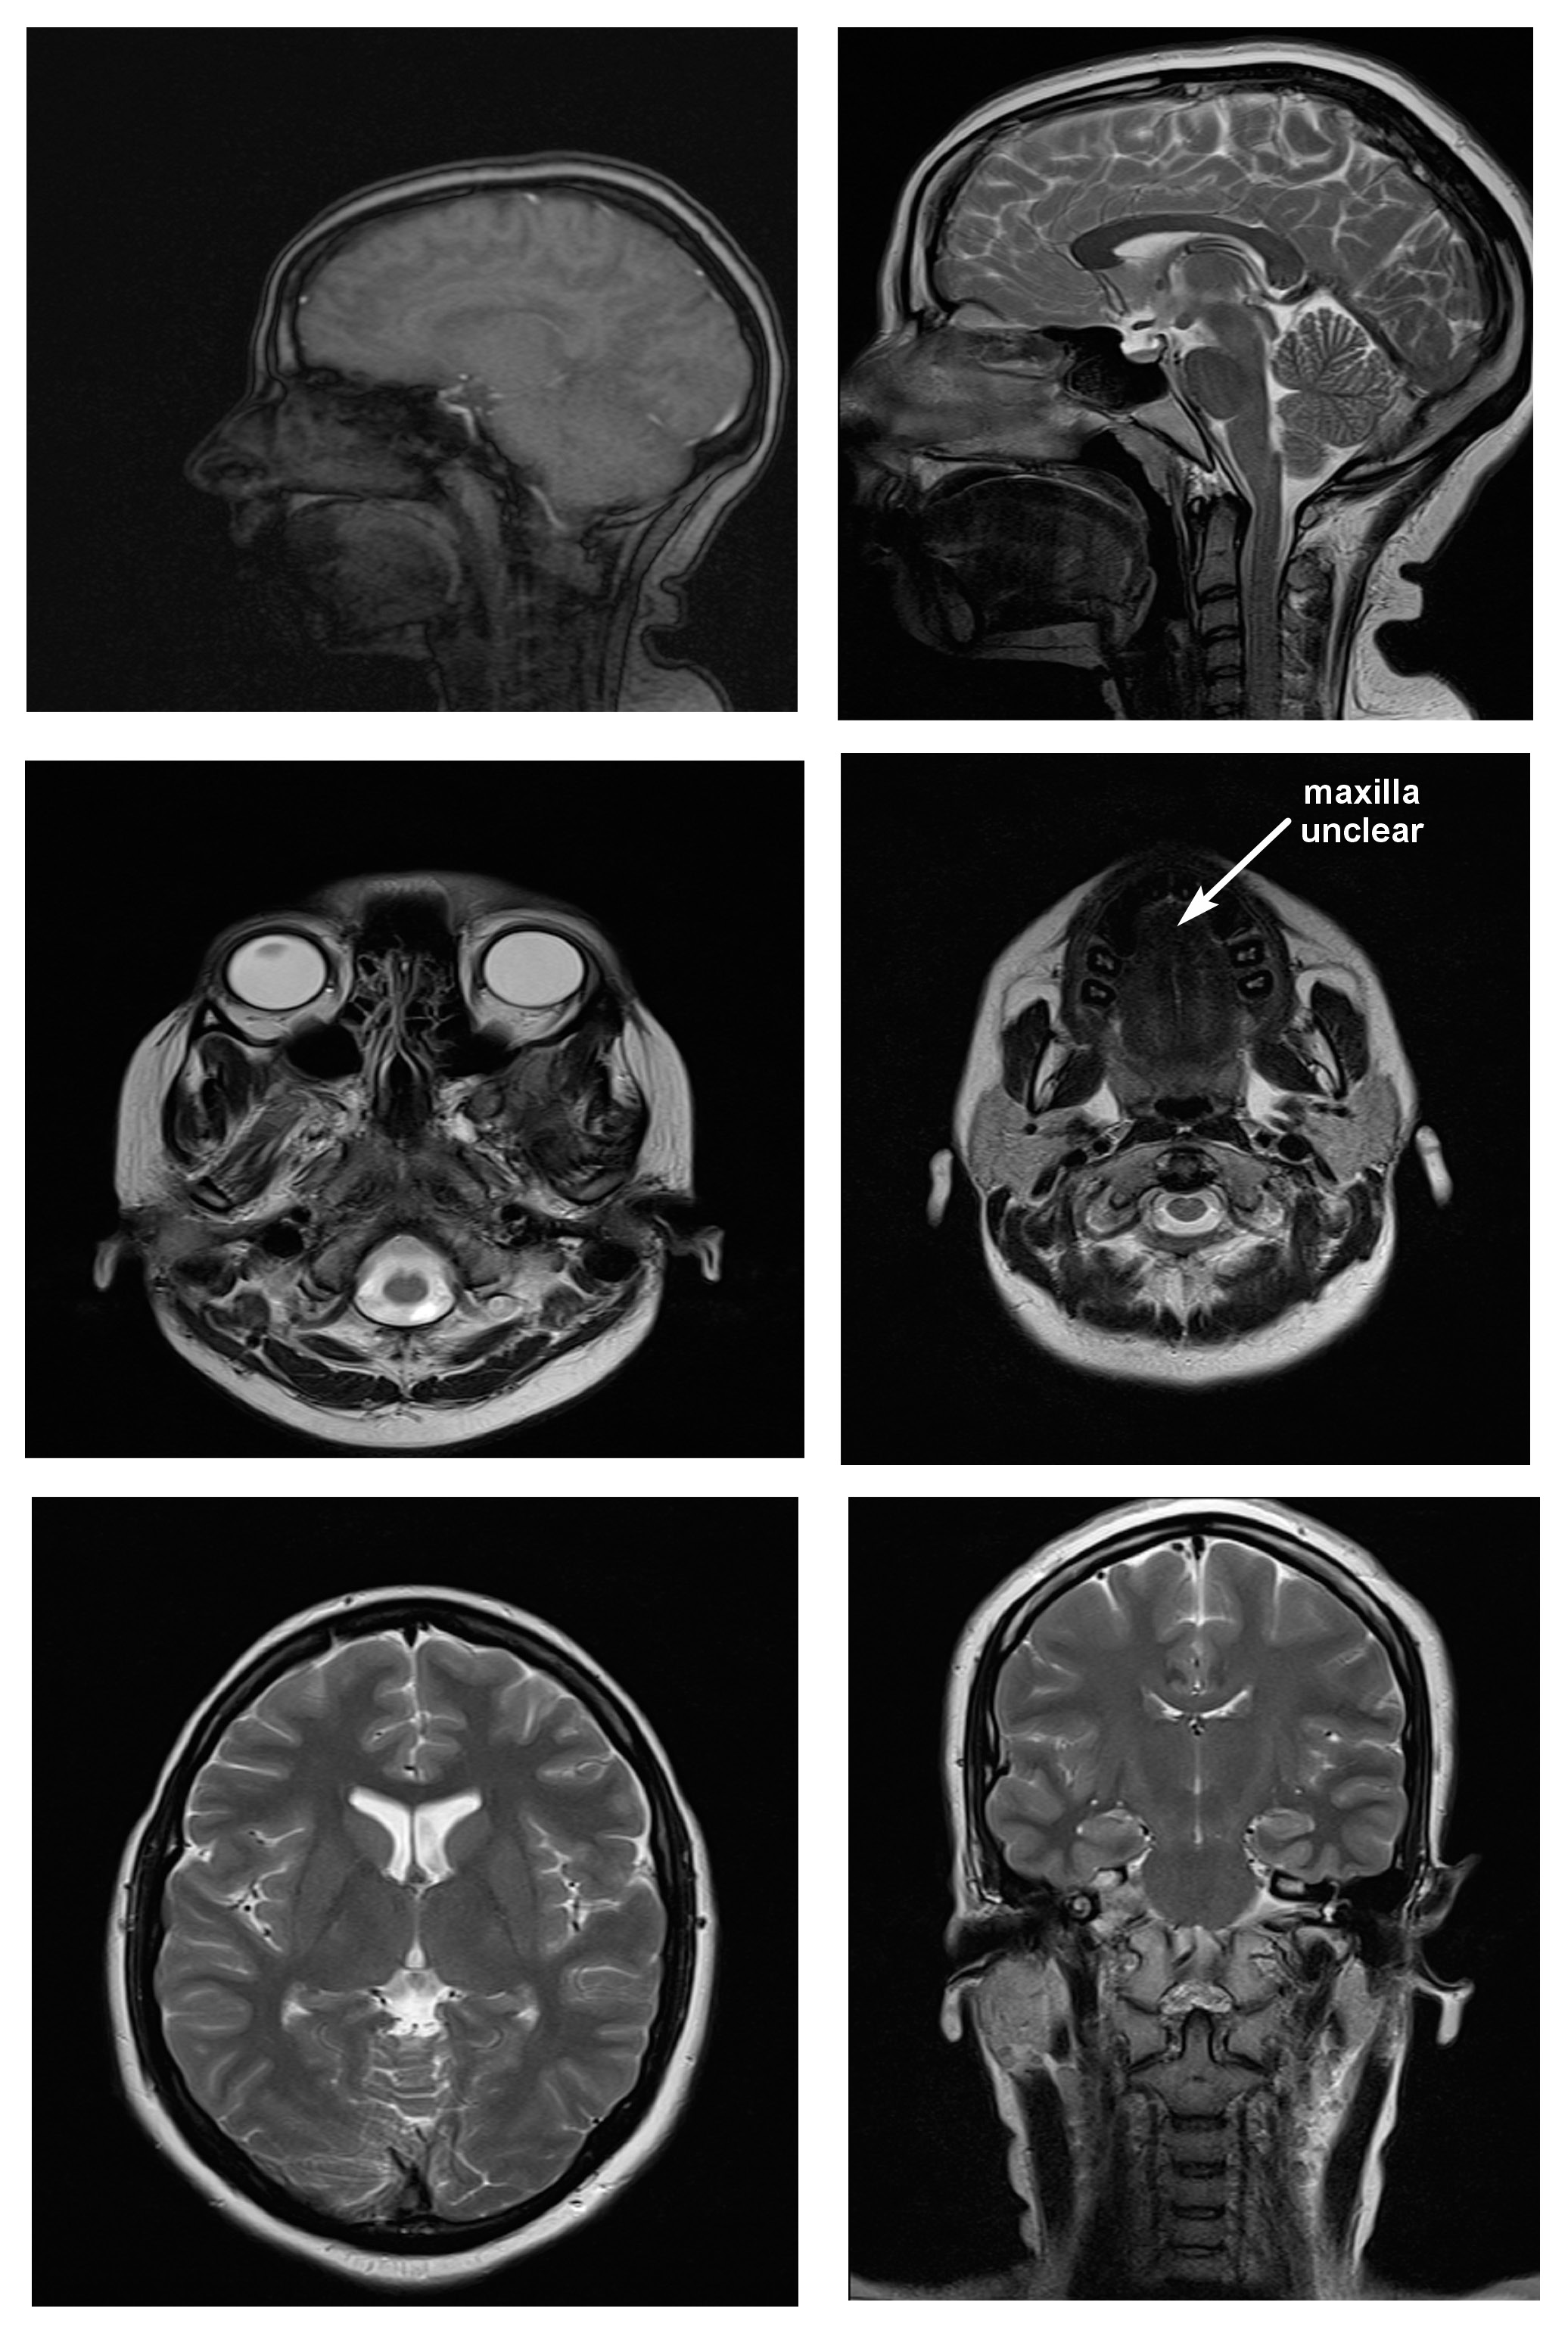

Magnetic resonance imaging scans were taken for all 38 subjects to study diagnostic image quality. Since the orthodontic appliances were securely bonded with orthodontic composite, there were no special precautions taken regarding the possible dislodgement and heating of the appliances, as previous studies had found changes in the temperature of the appliances to be clinically insignificant (within 1°C).16 The MRI scans for all types of bracket and retainer materials are shown in Figure 1, Figure 2, Figure 3, Figure 4, Figure 5, Figure 6, Figure 7, Figure 8, Figure 9, Figure 10. Non-diagnostic or unclear ROI are marked with arrows. None of the patients reported any discomfort or pain during MRI examination. The MRI scans were analyzed by a panel of 6 qualified and licensed radiologists, who assessed their diagnostic quality. The scans were compared with controls that included images from the archives of the Department of Radio-Diagnosis of Kamineni Institute of Medical Sciences. The radiologists ranked the images according to the distortion observed in the abovementioned ROI, using the modified receiver operating characteristic (ROC) analysis of distortion scoring system (Table 2), as described by Elison et al.17 In this method of distortion classification, a score of 3 represents the cut-off point for clinical usability. Images with a score of 3 have moderate distortion or artifacts, but they can still be used for diagnosis.

Stainless steel retainers in both the maxillary and mandibular arch had a mean distortion score of 2.00. The mean distortion scores at the anatomic sites were 2.16 for TMJ, and 2.00 for the tongue, the maxilla, the mandible, and the maxillary sinus, with only the posterior cerebral fossa having a score of 1.00. This means that there was minimal or no distortion for all ROI. Hence, the MR images with stainless steel retainers in the maxillary and mandibular arches were considered diagnostic.

Titanium retainers in the mandibular arch alone had a mean distortion score of 2.00. The mean distortion scores at the anatomic sites were 2.16 for TMJ, 2.00 for the tongue, the maxilla, the mandible, and the maxillary sinus, and 1.00 for the posterior cerebral fossa, which indicates that there was minimal or no distortion for all ROI. Hence, the MR images with titanium retainers in the mandibular arch alone were considered diagnostic. The results of this study are similar to the findings reported in studies by Shalish et al.,28 Beau et al.24 and Zhylich et al.25

The combination of a stainless steel retainer in the maxillary arch and a fiber-reinforced retainer in the mandibular arch had a mean distortion score of 2.00 and mean distortion scores of 2.00 for TMJ, the tongue, the maxilla, the mandible, and the maxillary sinus; the posterior cerebral fossa had a score of 1.00. Therefore, the MR images with this combination caused minimal or no distortion, and were considered diagnostic by the radiologists.

The combination of a stainless steel retainer in the maxillary arch and a titanium retainer in the mandibular arch received similar scores to the previous combination. Therefore, the MR images with a stainless steel retainer in the maxillary arch and a titanium retainer in the mandibular arch were considered diagnostic.